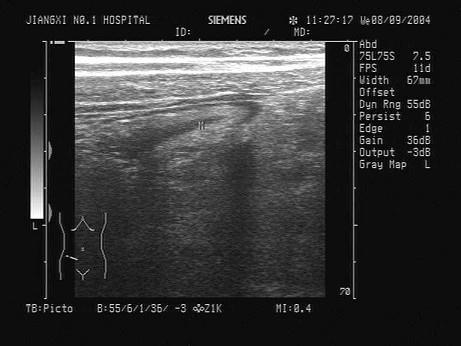

一腹痛患者,根据右下腹声像图表现,最可能的诊断是?(?)A.肠梗阻B.阑尾炎C.正常阑尾D.结肠癌E.肠套叠

问题 一腹痛患者,根据右下腹声像图表现,最可能的诊断是?(?)

选项 A.肠梗阻 B.阑尾炎 C.正常阑尾 D.结肠癌 E.肠套叠

答案 B